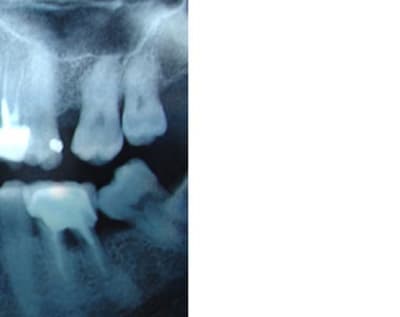

Ps: on peut noter le tartre encore présent sur la face mesiale de la 38 versée/mésialée.... on fera ça + tard lors de la litho/laser. Ca prouve bien que malgré tous les handicaps cumulés par ces 2 dents le seul traitement local a déjà été trés efficace.

oui on voit bien la corticalisation preuve que tout est au repos au niveau du parodonte profond ....